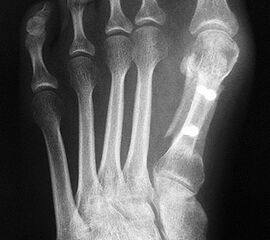

Die Röntgenaufnahmen (Abbildung 1) zeigen den Fuß einer 34 jährigen Patientin nach Exostosenabtragung. Der erhöhte intermetatarsale Winkel wurde durch eine alleinige Abtragung der Exostose nicht reduziert. Als weiterer Risikofaktor für ein Rezidiv liegt ein pathologischer Gelenkwinkel vor. Der intermetatarsale Winkel von 18 Grad kann durch eine basisnahe Osteotomie gut korrigiert werden. Da durch die gleichzeitige distale Korrektur des Gelenkflächenwinkels mithilfe einer Reverden-Green Osteotomie ein Längenverlust von ca. 2-4 mm einhergeht, bot sich als proximales Korrekturverfahren die basisnahe Open-wedge Osteotomie an, um bezüglich der Länge des Metatarsale I neutral zu bleiben (Abbildung 2). Die Kombination zweier verkürzender Verfahren (z.B. Lapidus und Reverden-Green) würden zu einem sehr kurzen ersten Strahl führen, mit dem Risiko einer Transfermetatarsalgie. Übersteigt die Verkürzung des Metatarsale I 2 mm, steigt das Risiko für die Entwicklung einer Transfermetatarsalgie deutlich an 8. Die durchgeführte Revision zeigt eine gute Stellung des 1. Strahls bei zentriert stehendem Gelenk.